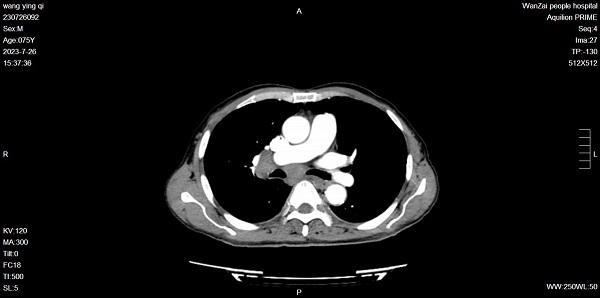

患者是一名74岁的男性,体检肺部CT发现右肺占位伴纵隔淋巴结转移,查体无特殊。

肺部增强CT提示隆突下及右肺门肿大淋巴结